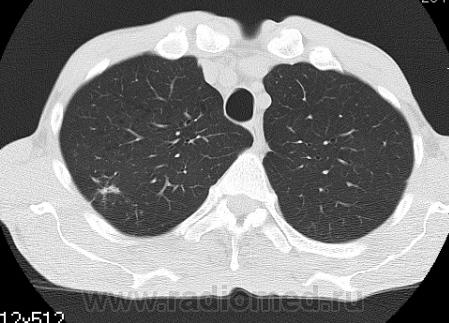

На фоне консолидации полость без содержимого. Может быть всё что угодно, что сопровождается деструкцией. Нужны ещё томограммы в лёгочном окне.

Изображения выставлены все. Ваше мнение уважаемые коллеги?

Туберкулёз.

Туберкулёз?

Это КТ 2-летней давности и попало оно мне в руки, после недавнего прохождения контроля пациентом, когда мы стали перед вопросом о специфическом / не специфическом процессе.

Тогда, пациента 2 месяца лечили от пневмонии, лечили интенсивности, стационарно, в серьёзном учреждении.

Предположу аспергиллез